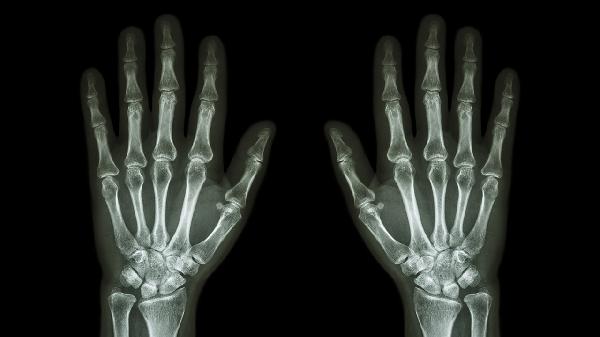

双手中指关节肿痛可能与骨关节炎、类风湿关节炎、痛风性关节炎、外伤或腱鞘炎等因素有关。该症状通常由关节退变、免疫异常、尿酸沉积、机械损伤或肌腱劳损等机制引发,具体需结合临床检查判断。

骨关节炎多见于中老年人群,与关节软骨磨损退化相关。长期重复使用手指关节可能导致局部骨质增生,表现为关节僵硬和活动时疼痛。早期可通过热敷缓解症状,医生可能建议使用硫酸氨基葡萄糖胶囊、双醋瑞因胶囊等药物保护软骨,严重时需考虑关节腔注射治疗。

类风湿关节炎属于自身免疫性疾病,晨僵超过1小时是其典型特征。免疫系统错误攻击滑膜组织会导致对称性关节肿胀,可能伴随低热和疲劳。确诊后需长期使用甲氨蝶呤片、来氟米特片等抗风湿药物,生物制剂如阿达木单抗注射液可用于控制炎症进展。

高尿酸血症患者易出现尿酸盐结晶沉积在关节腔,引发突发性红肿热痛。夜间发作常见,可能伴随皮肤发亮和触痛。急性期可使用秋水仙碱片、依托考昔片消炎镇痛,缓解期需配合非布司他片等降尿酸药物,同时限制高嘌呤饮食。

手指撞击或扭伤会造成关节囊及周围韧带损伤,表现为局部淤血和压痛。轻微挫伤可通过冰敷减轻肿胀,48小时后改用活血化瘀膏药如消痛贴膏。若存在骨折或脱位需进行手法复位,必要时用铝板固定制动。

频繁使用手指可能诱发屈指肌腱鞘炎症,表现为关节屈伸时有弹响感。狭窄性腱鞘炎在掌指关节处可触及痛性结节。早期可通过减少手指活动配合塞来昔布胶囊消炎,顽固性病例可能需要局部封闭注射或鞘管切开术。